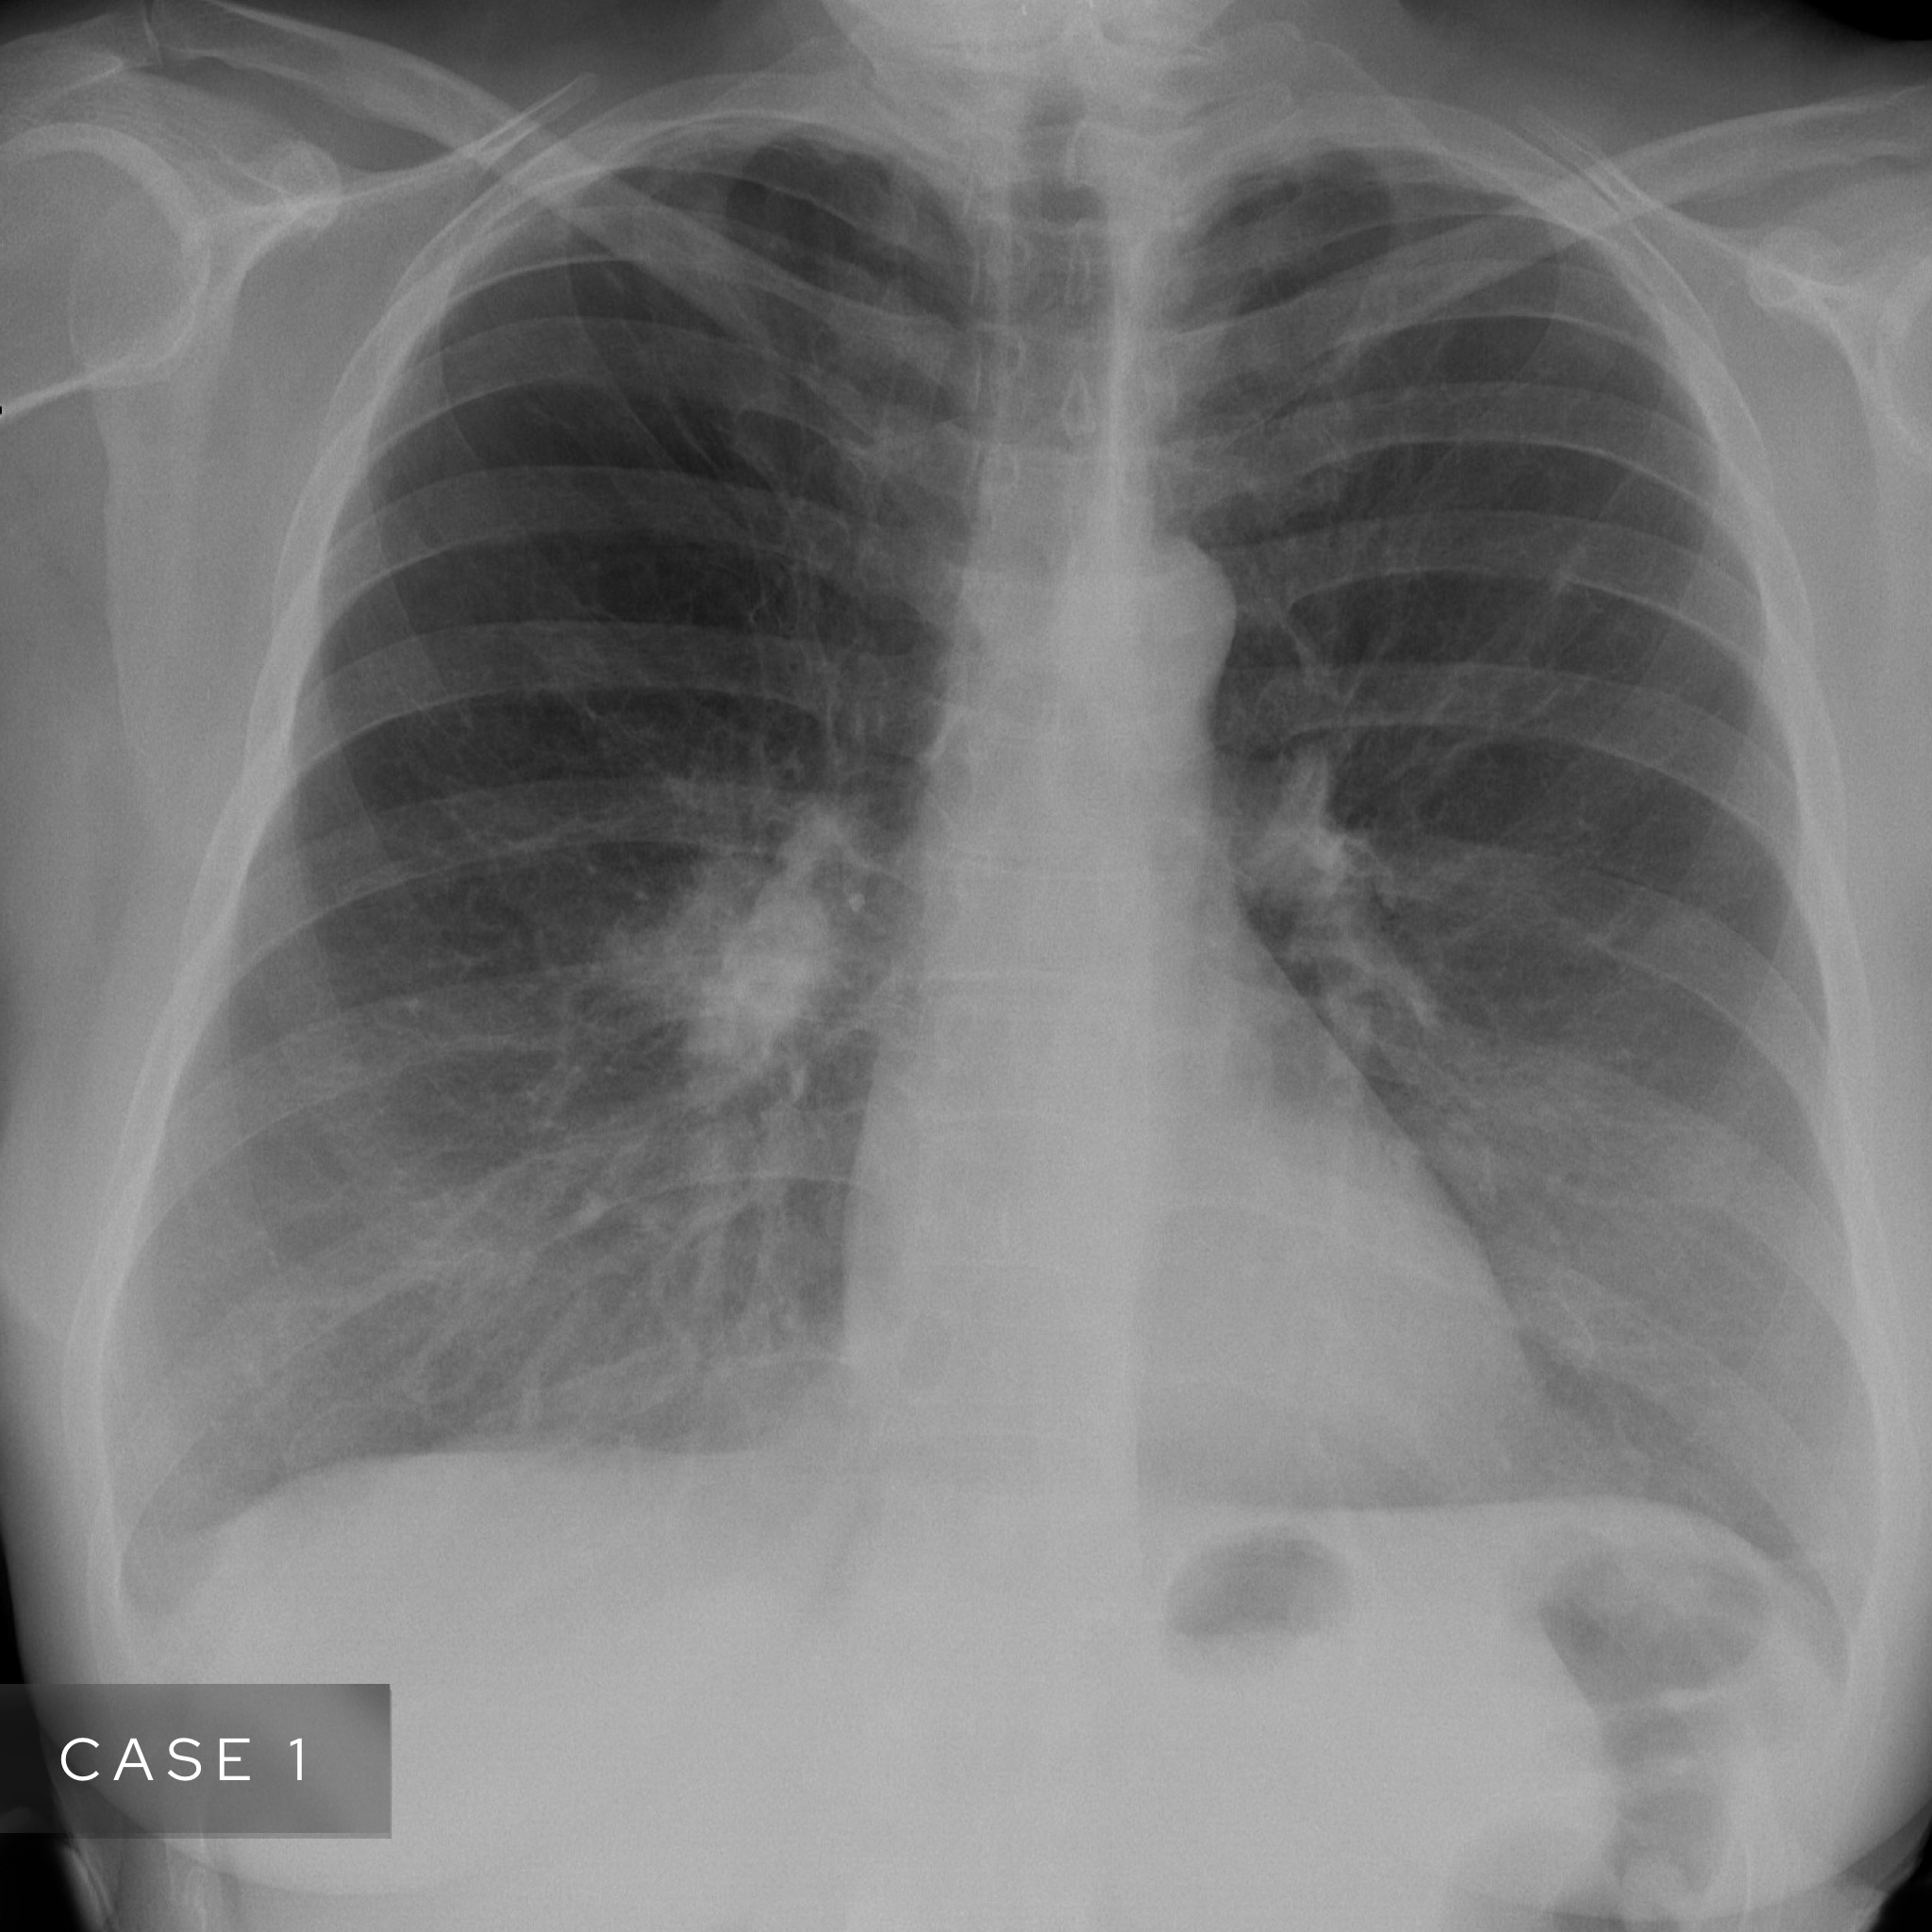

Case 1

A female in their 60s presents with unremitting cough on a background of weight loss. Have a look at the chest X-Ray below:

What is the most likely diagnosis? Choose from one of the following: